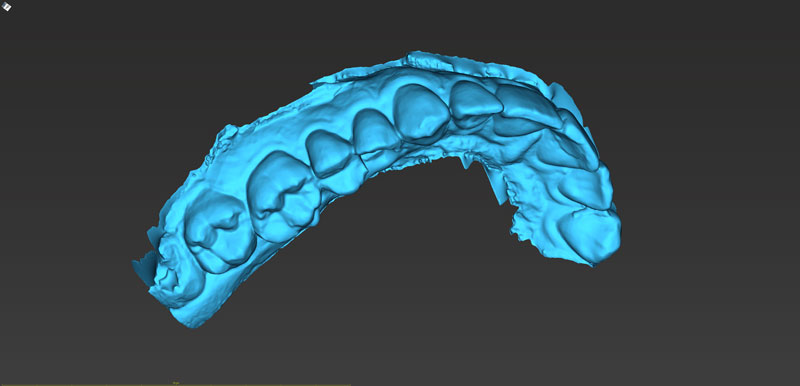

Ψηφιακό πλάνο θεραπείας

Κατευθυνόμενη τοποθέτηση εμφυτευμάτων

Είδη και ακρίβεια χειρουργικού οδηγού

Σχεδιασμός χειρουργικού οδηγού

- Ψηφιακό πλάνο θεραπείας

- Κατευθυνόμενη τοποθέτηση εμφυτευμάτων

- Είδη και ακρίβεια χειρουργικού οδηγού

- Σχεδιασμός χειρουργικού οδηγού